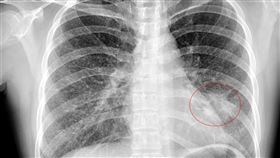

50歲男下背痛!X光一照「腫瘤超大顆」

肺癌是所有癌症死亡率占第一位的癌症,由於早期肺癌並沒...

2023/08/16 15:48